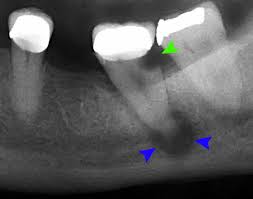

오래된 인레이에는 틈이 생기게 됩니다. 인레이는 완벽하게 sealing을 하지 못하기 때문이죠. 그 틈 사이로 충치가 진행되어 2차우식이 발생될 수 있습니다. 위 엑스레이 사진을 보시면 초록색 화살표 쪽에 2차우식이 생긴걸 보실 수 있습니다. 그에 따라 신경이 감염되어 파란색 화살표의 염증이 생기게 되는 것이죠. 참고로 검정색 부분은 빈 공간으로 염증이나 충치의 부분을 나타냅니다. (출처: http://smilecreationdental.com/)